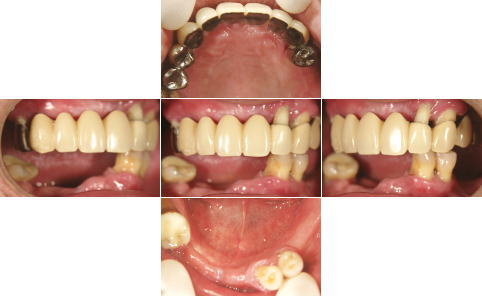

| 治療前 | 治療後 |

| 上顎、下顎共にグラツキの著しい歯は抜歯し、上顎はAll-on-4、下顎奥歯は通常のインプラントブリッジとしました。 | |